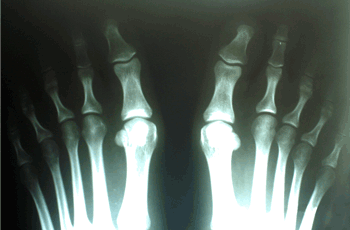

Caso 3: Hallux Valgus del Adulto

Ambos pies operados en el mismo acto quirúrgico.